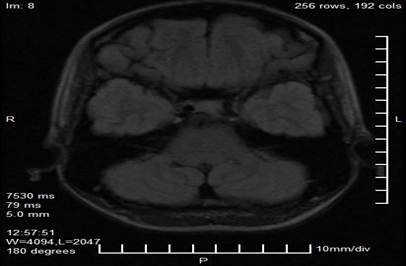

Los estudios complementarios incluyeron una resonancia magnética de cráneo con protocolo neurooftalmológico, la cual reveló una imagen nodular, lobulada y bien delimitada en proyección de la glándula pineal, con dimensiones de 29 mm × 28 mm × 27 mm. La lesión presentaba características de señal heterogénea, con áreas de hiperintensidad en secuencias T1 y T2 sugestivas de componente hemorrágico o vascular, y evidenciaba efecto compresivo sobre el tectummesencefálico y los colículos superiores. No se observaron signos de hidrocefalia obstructiva ni hipertensión intracraneal en los cortes obtenidos (Figuras 2 y 3).

Figura 2. Corte axial de resonancia magnética en secuencia T1 donde se observa lesión nodular lobulada en proyección de la glándula pineal (flecha), con hiperintensidad heterogénea sugestiva de componente hemorrágico o vascular.